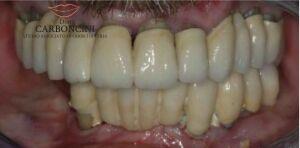

Riabilitazione protesica su impianti in paziente con malattia parodontale

Il paziente aveva perso la maggior parte dei denti a causa della malattia parodontale , e stava perdendo i restanti per lo stesso motivo. Dopo le estrazioni furono inseriti 4 impianti nell’arcata superiore e 4 nell’arcata inferiore seguendo il protocollo del carico immediato.

Restauro protesico finale eseguito con 8 impianti e 22 corone in oroceramica.

DOPO